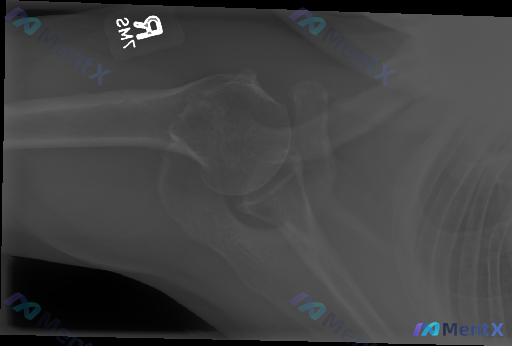

整理了一份比较有意思的影像分析材料: 一张右侧肩关节正位X光片,常规放射科报告写的是“未见明显骨性结构异常、急性骨折脱位、慢性退变或钙化性肌腱炎征象”——简单说就是“基本正常”。 但这份材料的背景提示是「存在异常(Abnormality present)」。 深度分析里提了几个点很戳人: 1. 常规...